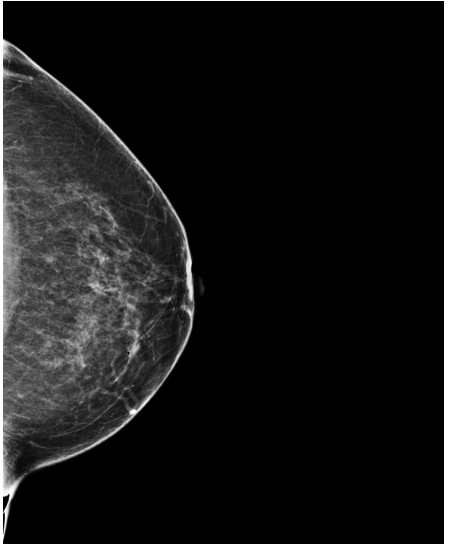

Refer to caption

(a) FeatAlign

(b) FeatAlignReg

(c) ImgFeatAlign/ImgAlign

(d) FeatAlign

(e) FeatAlignReg